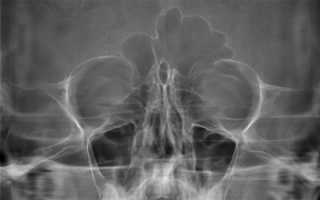

Рентгенограмма приносовых синусов.

Расшифровывая снимок пациента с синуситом, можно сразу же провести более детальную дифференциальную диагностику, согласно его локализации и распространенности.

Рентгенологическая классификация синуситов:

По локализации:

- Гайморит – локализация в гайморовых (верхнечелюстных) пазухах.

- Фронтит – патология лобных синусов.

Сфеноидит – воспаление пазухи клинообразной кости.

- Этмоидит – воспалительный процесс в синусах сосцевидного отростка.

По распространенности:

- Моносинусит – процесс протекает только в одном синусе.

- Полисинусит – в воспаление втянуты несколько пазух разных костей.

- Гемисинусит – поражение всех пазух с одной из сторон (правой или левой).

- Пансинусит – одновременное втягивание в воспалительный процесс всех околоносовых пазух.